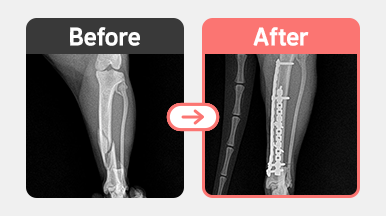

[요골 골절 수술] 푸들 / 4살 / 좌측 radius 골절

[요골 골절 수술] 말티푸 / 1살 / 우측 radius 횡골절 / plate 내고정술

[경골 골절 수술] 러시안블루 / 2살 / 좌측 tibia 복합골절 / 이중 plate 고정